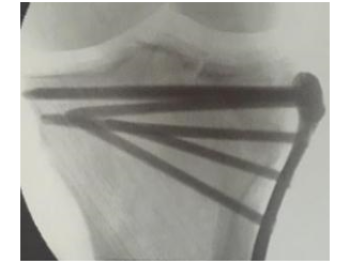

Ortopedik Travma 3252 OkunmaPatella çıkığı

Patella çıkığı

Patella (Diz kapağı) Çıkığı 9 OkunmaMPFL Rekonstrüksiyonu

Medial Patellofemoral Rekonstrüksiyon